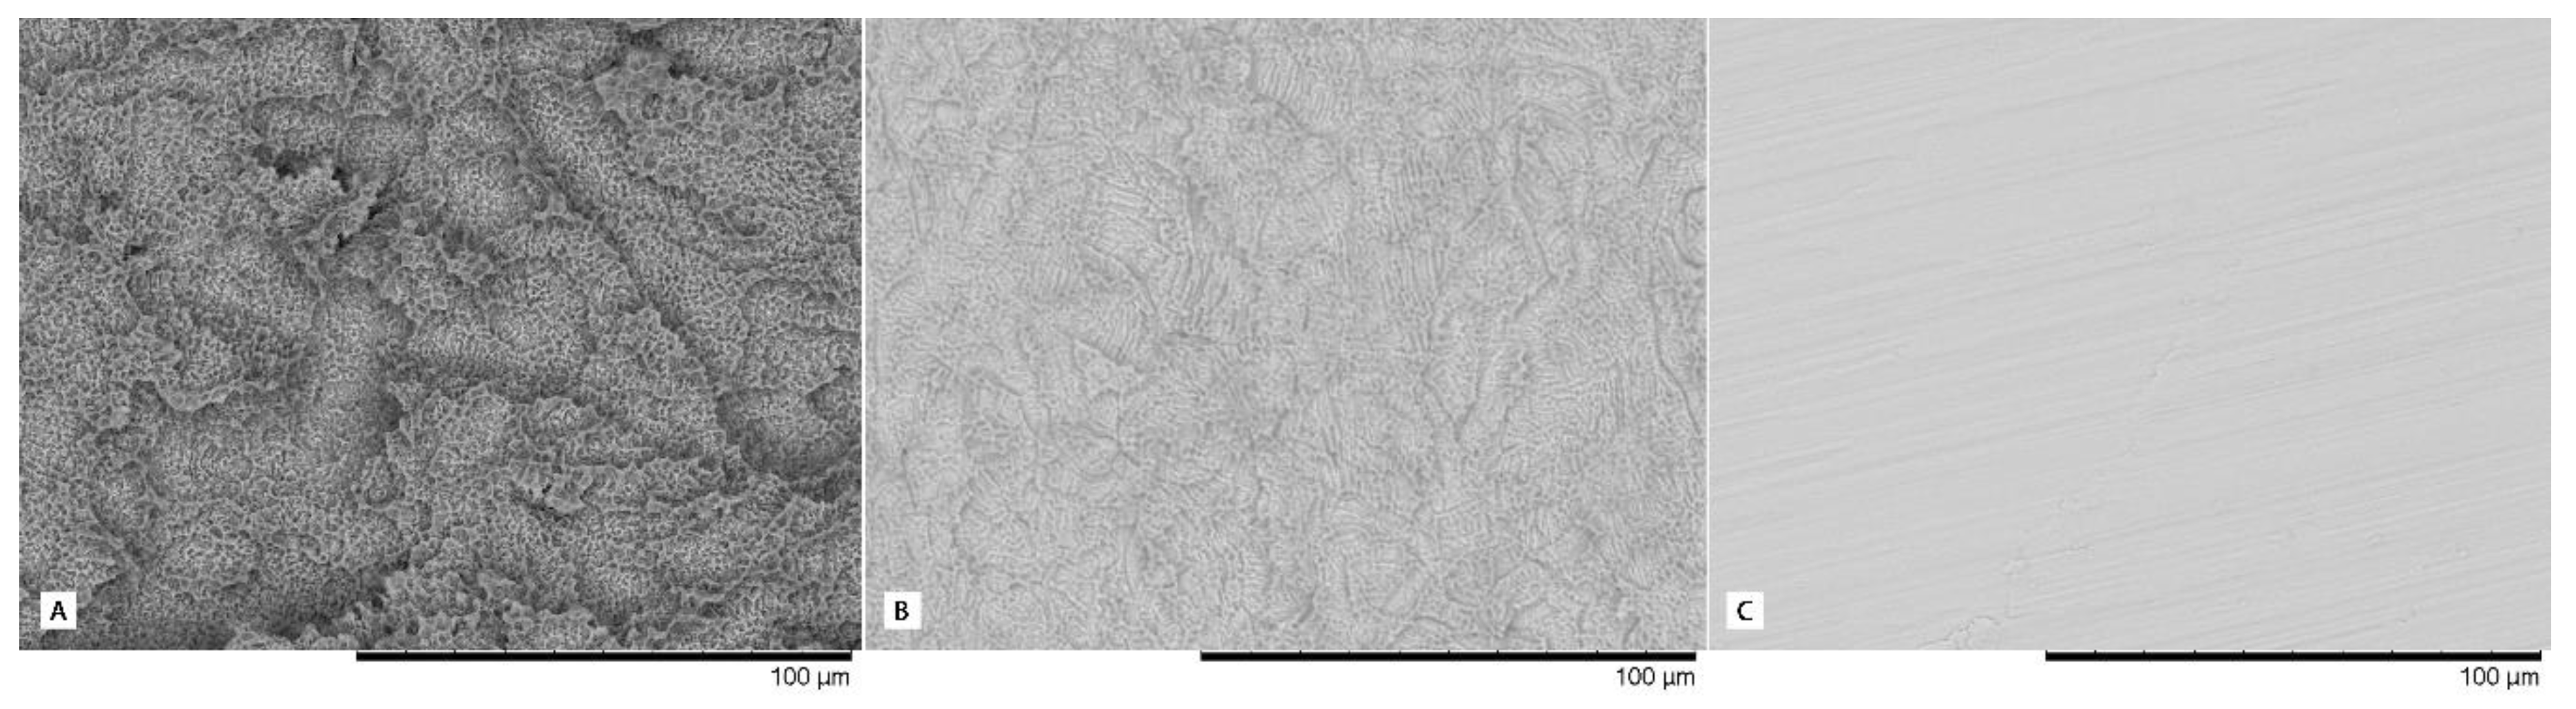

The IPX implant surface received a surface conditioning treatment consisting of a mixed method (mechanical and chemical; The Nanoblast Plus® technique) for improving implant surface topography through two consecutive processes: aluminum oxide spraying and triple acid etching. This method was patented by the manufacturer Galimplant SLU (Sarria, Lugo, Spain). The SLA (Sandblast, Large-Grit, Acid-Etching) method is a method patented by Straumann (Straumann AG, Basel, Switzerland) that induces surface erosion by applying a strong acid onto the blasted surface. This treatment combines blasting with large-grit sand particles and acid etching sequentially to obtain macro roughness and micro pits. The roughness characteristics of each surface can be observed with a magnification of 1000× in Figure 2.

Figure 2.

High magnification images (1000×) of the surfaces evaluated; (A) SLA® Surface, (B) Nanoblast Plus® Surface, and (C) IPX Machined Surface.